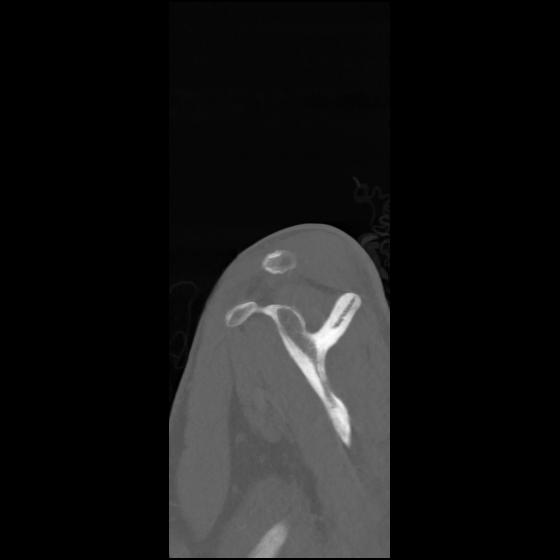

24 ANGIO,CE,Sag-MIP,5.000,ANGIO,Sag-MIP,